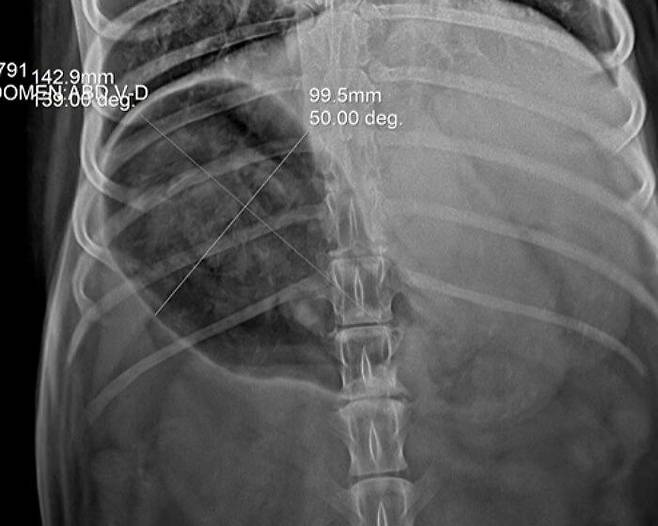

강아지 배 속 엑스레이 사진에 포착된 거북이 등껍질

걱정된 집사가 급히 병원을 찾았는데요. 엑스레이 검사 결과 허스키 강아지 모의 배 속에는 아주 선명한 거북이 등껍질 두 개가 자리 잡고 있었습니다.